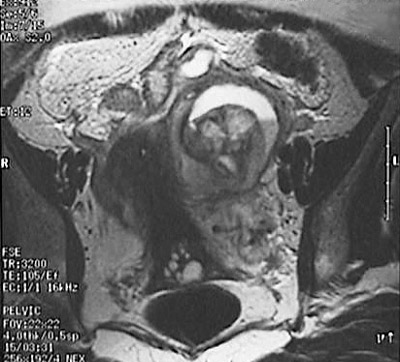

![]() | This magnetic resonance imaging (MRI) scan of the pelvis in axial view demonstrates a large left adnexal mass with a fluid-fluid level. The mass displaces the uterus. This proved to be an endometrioma, or a cyst derived from a focus of endometriosis that continued to hemorrhage into the cyst. |